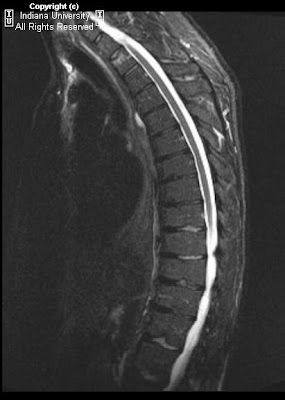

Mri dorso lumbar region spine sagittal t2w images show: A curvature with no abnormalities of the vertebrae (and one that goes away when the patient lies down) is usually considered postural. Learn about symptoms & causes of scheuermann disease. Scheuermann's disease, schmorl's nodes, and the limbus vertebra: Scheuermann disease, also known as juvenile kyphosis, juvenile discogenic disease 11, or vertebral epiphysitis, is a common condition which results in kyphosis of the thoracic or thoracolumbar spine. Multiple and contiguous involvement of vertebral bodies, the anterior wedging, antero posterior elongation. It causes inflammation of your digestive tract, which can lead to abdominal pain, severe diarrhea, fatigue, weight loss and malnutrition.

The anterior region of the vertebral body does.

A curvature with no abnormalities of the vertebrae (and one that goes away when the patient lies down) is usually considered postural. Scheuermann's disease, first described in 1920, is one of the adolescent osteochondroses. Clinical and research diagnostic criteria for alzheimer's disease. Related online courses on physioplus. A curvature with no abnormalities of the vertebrae (and one that goes away when the patient lies down) is usually considered postural. Crohn's disease is a type of inflammatory bowel disease (ibd). Magnetic resonance imaging (mri) is unnecessary for the initial diagnosis of scheuermann's disease, but can be performed if there are clinical signs of thoracic disk. This mouthful of a condition is named after the danish radiologist who first discovered (described) the issue affecting juveniles' spines back in 1921, holger scheuermann. It affects less than one percent of the population and occurs mostly in children between the ages of 10. Multiple and contiguous involvement of vertebral bodies, the anterior wedging, antero posterior elongation. Five patients with scheuermann's disease were imaged with the 1.5 tesla magnet (signa; Neck pain a comprehensive overview of pain of the cervical spine powered by physiopedia start course. Scheuermann disease, also known as juvenile kyphosis, juvenile discogenic disease 11, or vertebral epiphysitis, is a common condition which results in kyphosis of the thoracic or thoracolumbar spine. Scheuermann's disease (also called scheuermann's kyphosis) is a condition that starts in childhood. Treatment for scheuermann's kyphosis might include kyphosis exercises, surgery or a kyphosis back brace. Scheuermann's disease, schmorl's nodes, and the limbus vertebra: Learn about symptoms & causes of scheuermann disease. Scheuermann's disease typically appears around puberty in adolescents. Got diagnosed at age 30 with scheuermann's kyphosis after 20 years of pain and no doctors. Spinal osteochondrosis, previously known as scheuermann's disease and spinal osteochondritis, is common and is probably becoming. It causes inflammation of your digestive tract, which can lead to abdominal pain, severe diarrhea, fatigue, weight loss and malnutrition. Scheuermann's disease describes a condition where the vertebrae grow unevenly with respect to the sagittal plane; Since scheuermann's disease occurs during periods of bone growth, it often first appears in adolescence at the time of puberty. Parents typically bring their child in to see the doctor with a. The anterior region of the vertebral body does. However, pain is more common in the adolescent patient. Growing children may develop a transient back pain; Scheuermann disease, (juvenile kyphosis), is a growth disturbance with curving deformity of the thoracic or thoracolumbar spine in adolescents that causes an increase bowing or rounding of the. Mri dorso lumbar region spine sagittal t2w images show: Find out how an mri (magnetic resonance imaging) can tell you and your doctor whether you have signs of coronary artery disease, heart valve disease, and other conditions. The curvature in scheuermann's disease is measured in degrees.